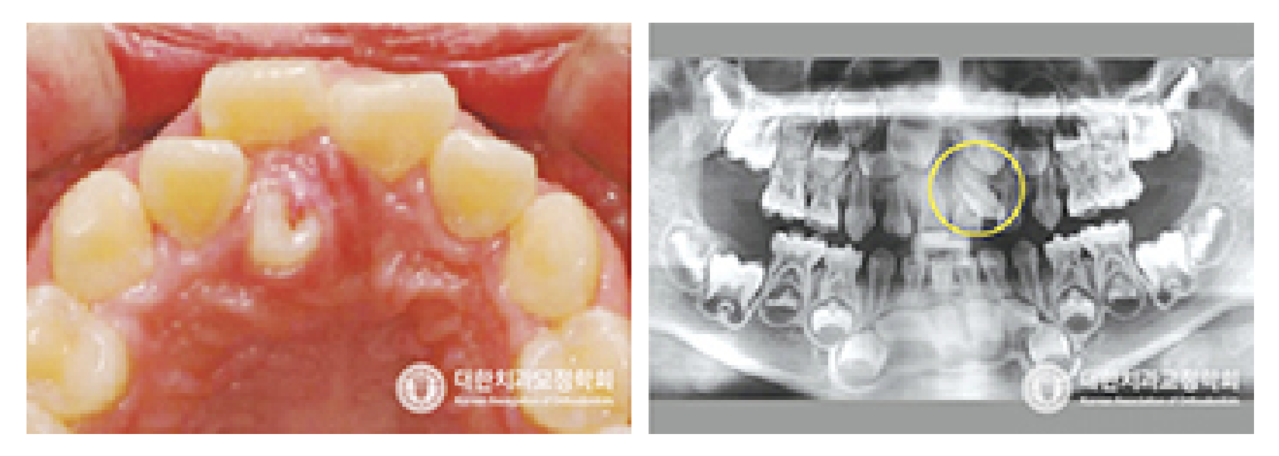

● 과잉치가 있는 경우

‘과잉치’라 함은 정상적인 치아 개수보다 더 많은 치아가 있는 경우를 말합니다. 과잉치가 있는 경우, 다른 영구치들이 정상적으로 맹출하지 못하거나 치아가 밀리면서 다른 위치로 맹출하게 되어 부정교합을 야기할 수 있습니다. 조기에 발견한다면 과잉치만 제거하는 등의 간단한 처치로 끝날 수도 있지만, 너무 늦어지면 더 큰 문제를 야기할 수 있습니다.

그러므로, 젖니를 영구치로 교환하는 시기에는 꼭 교정과 의사에게 상담을 받으시어 과잉치 여부를 체크하시고, 필요하다면 적절한 치료를 받으셔야 합니다.